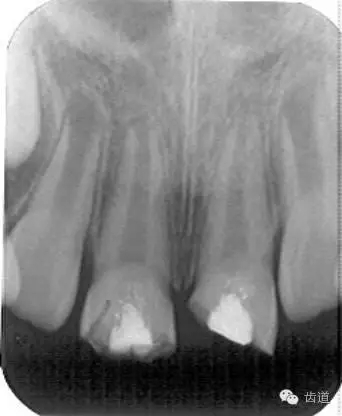

術(shù)后一個月

術(shù)后當(dāng)天

術(shù)后11個月

術(shù)后五個月